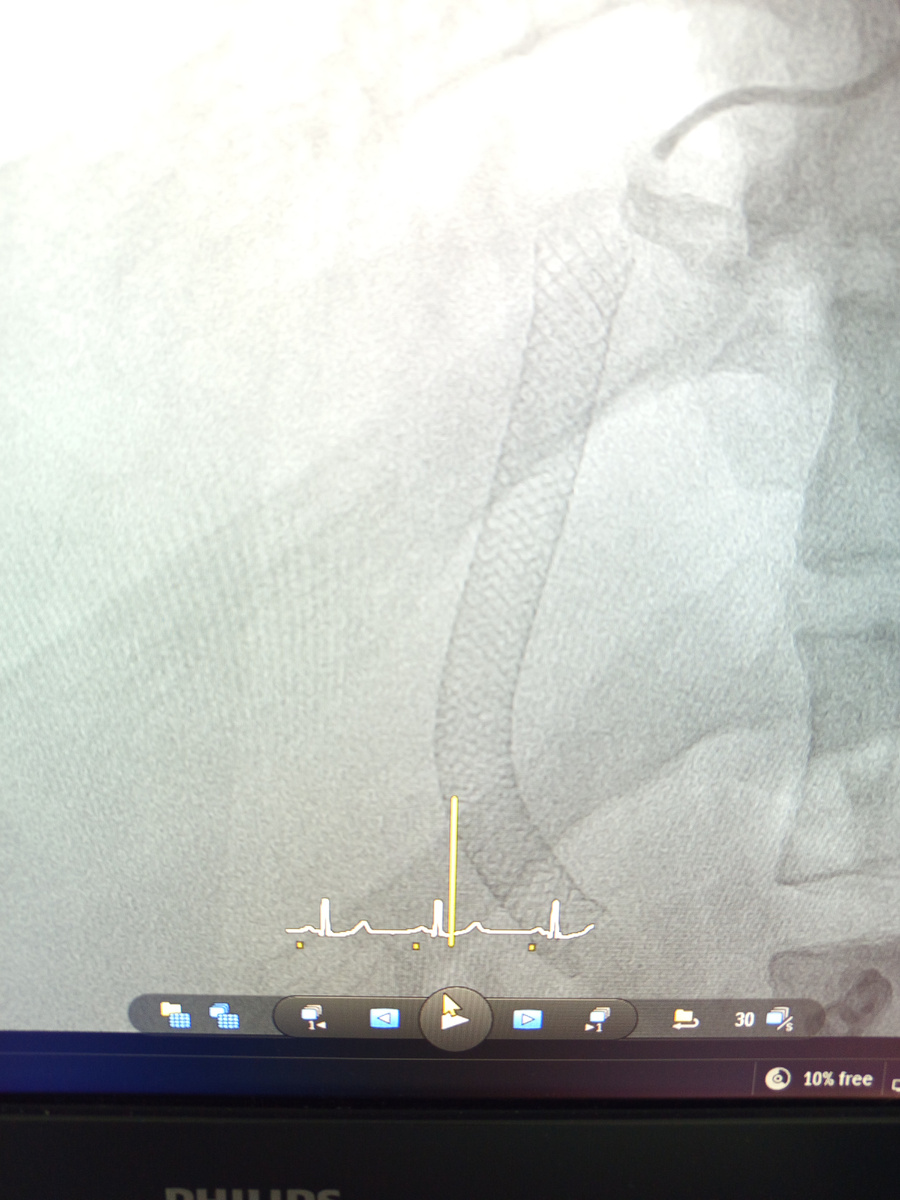

На фото предыдущий стент печеночный, стоит.

Воротная вена , после заведённых проводников.

Само рестентирование(повторный стент)

Итог:два стента , реканализация и еще месяцы жизни пациенту, а , может , и годы. На пересадку печени его не возьмут.